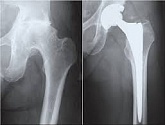

Hüftendoprothetik

In den späten Stadien der Arthrose des Hüftgelenks, mediale Frakturen des Schenkelhalses in der älteren Altersgruppe, ist die einzige Möglichkeit, sich zu erholen, das betroffene Gelenk durch eine künstliche Gelenkarthroplastik zu ersetzen.

Diese Methode ermöglicht es Ihnen, die Gliedmaße, das volle Volumen der Bewegungen im betroffenen Gelenk, zurückzugeben, um von ständigem Schmerz und Knirschen während der Bewegungen zu sparen und folglich den Patienten zu einem vollen aktiven Leben zurückzubringen.

Im Folgenden werden Röntgenaufnahmen und Fotografien vorgestellt, die das Ausmaß der Bewegung im betroffenen Gelenk vor und nach der Operation zeigen.